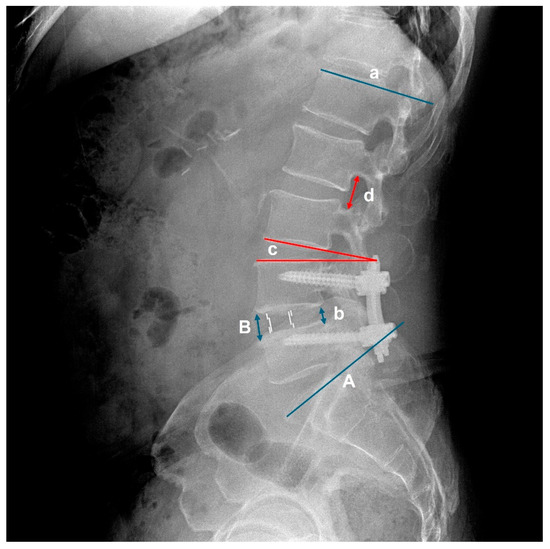

Revisional Endoscopic Foraminal Decompression via Modified Interlaminar Approach at L5-S1 after Failed Posterior Instrumented Lumbar Fusion in Elderly Patients

by Zheng Cao, Zhenzhou Li, Hongliang Zhao, Jinchang Wang and Shuxun Hou

Bioengineering 2023, 10(9), 1097; https://doi.org/10.3390/bioengineering10091097 - 19 Sep 2023

Elderly people usually have poorer surgical tolerance and a higher incidence of complications when undergoing revision surgery after posterior instrumented lumbar fusion (PILF). Full-endoscopic transforaminal surgery is a safe and effective option, but sometimes, it is difficult to revise L5-S1 foraminal stenosis (FS) [...] Read more.

Elderly people usually have poorer surgical tolerance and a higher incidence of complications when undergoing revision surgery after posterior instrumented lumbar fusion (PILF). Full-endoscopic transforaminal surgery is a safe and effective option, but sometimes, it is difficult to revise L5-S1 foraminal stenosis (FS) after PILF. Therefore, we developed full-endoscopic lumbar decompression (FELD) at the arthrodesis level via a modified interlaminar approach under local anesthesia. This study aimed to describe the technical note and clinical efficacy of the technique. Eleven patients with unilateral lower limb radiculopathy after PILF underwent selective nerve root block and then underwent FELD. Magnetic resonance imaging (MRI) and computer tomography (CT) were performed on the second postoperative day. Their clinical outcomes were evaluated with a Visual analog scale (VAS) of low back pain and sciatica pain, Oswestry disability index (ODI), and the MacNab score. Complete decompression was achieved in every case with FELD without serious complications. Postoperative VAS of sciatica pain and ODI at each time point and VAS of low back pain and ODI after three months postoperatively were significantly improved compared with those preoperative (p < 0.05). According to the MacNab criteria, seven patients (63.6%) had excellent results at the two-year follow-up, and four patients (36.4%) had good results. No patients required further revision surgery. FELD, via a modified interlaminar approach, is effective for treating unilateral L5-S1 FS after PILF in elderly people. Full article

Show Figures

Figure 1